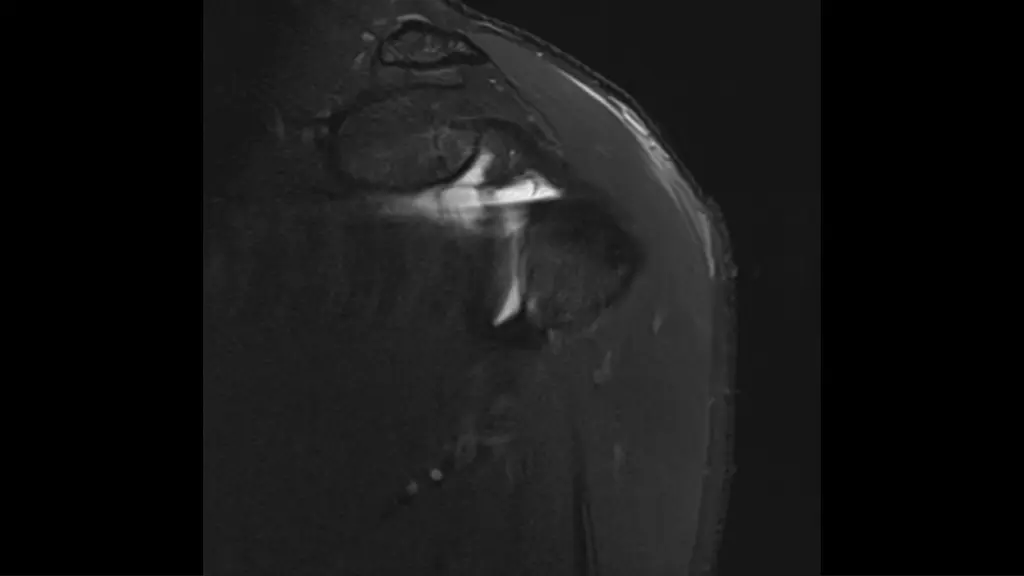

1. M31, M31, recurrent recurrent shoulder shoulder dislocation dislocation, last time , last time one one week week ago ago